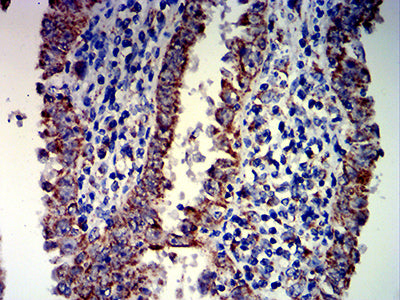

Immunohistochemical analysis of paraffin-embedded human liver cancer tissues using PAX8 mouse mAb with DAB staining.

Immunohistochemical analysis of paraffin-embedded human endometrial cancer tissues using PAX8 mouse mAb with DAB staining.